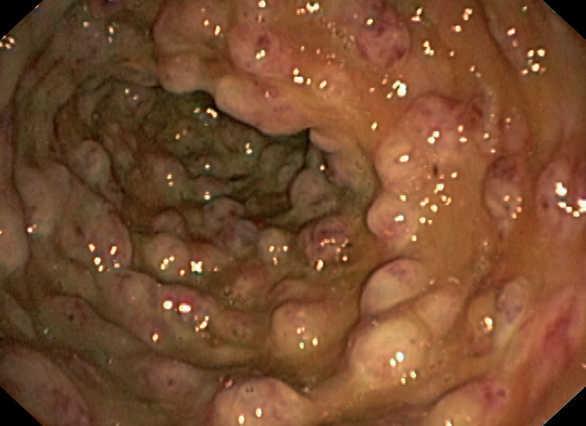

Durante el ingreso, la paciente desarrolló fiebre, dolor abdominal, vómitos y deposiciones diarreicas. Se realizaron coprocultivos, estudio de parásitos, determinación de toxina para Clostridium difficile y antigenemia para citomegalovirus (CMV) en dos ocasiones, que resultaron negativas. Se realizó TC abdominal (figura 1) en la que se observó engrosamiento de la pared del colon con oclusión de la luz desde el ciego hasta la unión recto-sigmoidea compatible con pancolitis difusa. Se solicitó fibrocolonoscopia (figura 2) en la que se objetivó una mucosa edematosa con múltiples lesiones nodulares blandas compatibles con neumatosis coli. En la biopsia de colon se detectaron inclusiones víricas que se confirmaron para CMV por inmunohistoquímica (figura 3). La tercera determinación de antigenemia para CMV fue positiva y el diagnóstico definitivo fue de colitis por CMV.

Figura 2. Fibrocolonoscopia